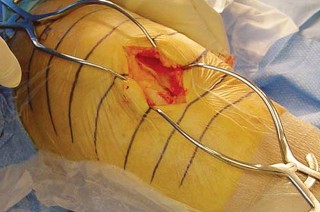

2. الوضع الجراحي والتعرض

- الوضع: يُوضع المريض في وضع الاستلقاء (Supine positioning) مع وضع كيس رمل أسفل الركبة أو حامل للساق يسمح بثني وفرد الركبة. يجب أن يكون الوضع مماثلاً لوضع جراحة TKA، مع استعداد لتحويل الإجراء إلى TKA إذا لزم الأمر.

- العاصبة (Tourniquet): تُستخدم عاصبة وتُوضع في أعلى الفخذ لتقليل النزيف.

-

الشق الجراحي:

يُستخدم شق طولي في الجانب الإنسي (الداخلي) من الركبة. يجب أن يكون الشق كبيرًا بما يكفي لتوفير رؤية جيدة للمفصل الرضفي الفخذي وإمكانية التحويل إلى TKA.

- فتح المفصل (Arthrotomy): يكون الفتح خطيًا وموازياً لألياف الوتر الرضفي، ويمتد إلى عظم الظنبوب وإلى الجزء السفلي من الرضفة.

- تحرير الأنسجة الرخوة: يتم قطع الغضروف الهلالي لتحرير الأنسجة الرخوة من عظم الظنبوب، ويتم تطوير سديلة تحت السمحاق في نمط دائري حول الظنبوب. يُمدد هذا التحرير خلفيًا لضمان توازن الأربطة.